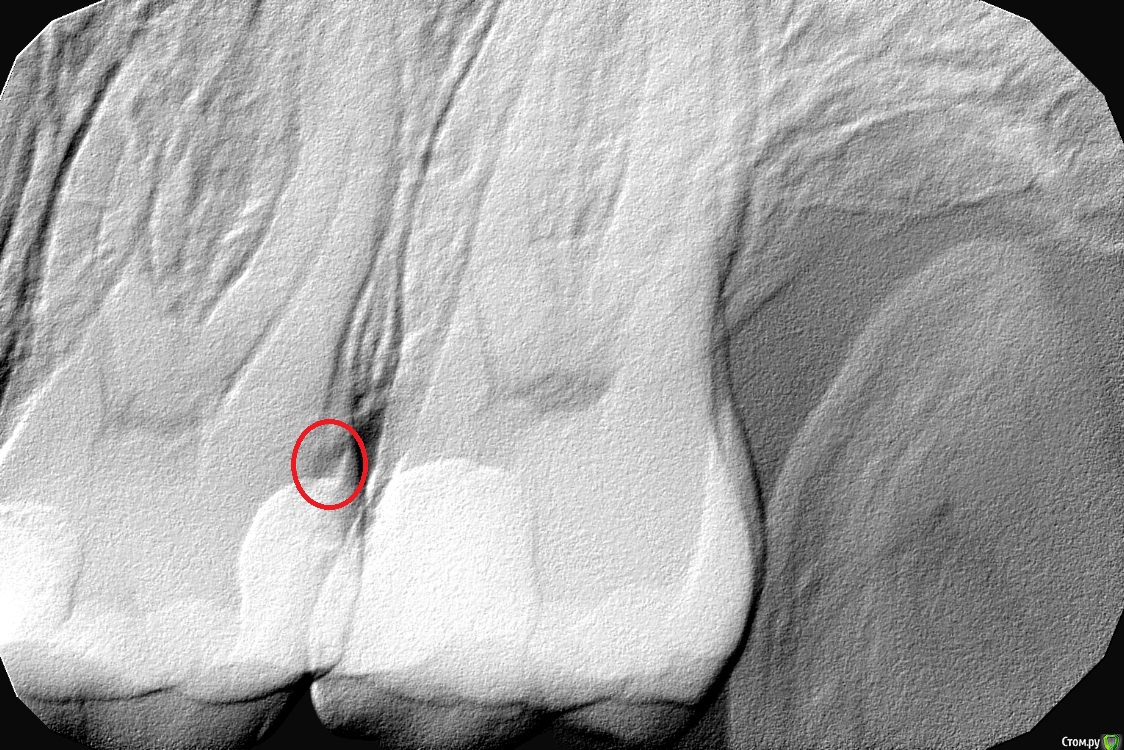

apex locator Опубликовано 10 марта, 2017 Поделиться Опубликовано 10 марта, 2017 Года два назад делал пломбы на эти двух зубах, которые вы видите во вложении. Сейчас 26 зуб ноет, терпимо, но чувствуется, что там что-то не так (красным выделил подозрительный участок). Врач говорит, что лучше ставить не пломбу за 5 т.р., а керамическую вкладку за 17 т.р. Скажите, есть ли смысл в этих вкладках? Мне первый раз такое предлагают. Дорого, потому хочу все взвесить перед тем, как решиться на такую сумму. Ссылка на комментарий

AndyAndy Опубликовано 10 марта, 2017 Поделиться Опубликовано 10 марта, 2017 Керамическая вкладка безусловно лучше композитной пломбы: не имеет усадки, не истирается. Как следствие - продолжительность жизни такой реставрации и зуба дольше. Но ни пломба, ни вкладка зуб "не лечат". Место, которое вы обвели, действительно является подозрительным на предмет кариеса Ссылка на комментарий